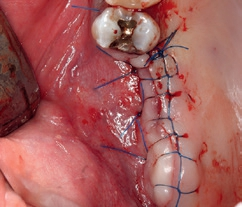

In Lokalanästhesie wurde mit einer vertikalen Entlastung an Zahn 24 und einer marginalen Schnittführung 25, welche mittig im Bereich der Linea alba nach distal fortgeführt wurde, ein Mukoperiostlappen gebildet. Der dreidimensionale Defekt wurde mit einer Präparation nach palatinal dargestellt und das Titangitter auf seine Passform kontrolliert. Bereits zum jetzigen Zeitpunkt erfolgte eine Periostschlitzung für einen späteren spannungsfreien Wundverschluss. Nach Ausdünnung des Knochenfensters mit dem Safescraper wurde das bukkale Fenster für den externen Sinuslift präpariert und die Schneider-Membran angehoben. Diese zeigte sich als vollständig intakt. Aufgrund des großen Augmentationsvolumens wurde zusätzlich retromolar in regio 47/48 mit einem Trepanbohrer autologer Knochen entnommen (Abb. 2) und mit einer Knochenmühle in kleine Knochenspäne zerkleinert. Das Mischverhältnis im Bereich der Augmentation lag bei einem Anteil von 50% autologem Knochen mit 50% bovinem Knochenersatzmaterial (Bio-Oss, Geistlich) (Abb. 3), wobei im Bereich der Kieferhöhle mit etwas mehr DBBM und nur einer geringeren Menge an autologen Knochenchips gearbeitet wurde. Nach dem Auffüllen des Sinus (Abb. 4) wurde das individuelle Titangitter mit leicht rüttelnden Bewegungen auf den Defekt gesetzt und dessen Passform an den Füßchen am Rande des Gitters überprüft. Anschließend wurde es mit 2 Osteosyntheseschrauben lagestabil fixiert (ADS Schrauben, American Dental) (Abb. 5) und zusätzlich mit einer Kollagenmembran abgedeckt (Biogide, Geistlich) (Abb. 6). Es erfolgte ein primärer Wundverschluss mit 2 tiefen Matratzennähten und einer fortlaufenden Naht (Seralon 5/0, Serag-Wiessner) (Abb. 7). Postoperativ wurde die Patientin gebeten, für 2 Wochen das Schnäuzen der Nase zu unterlassen.

Darüber hinaus bekam sie ein Antibiotikum (Amoxicillin 1000 mg, 1/1/1 über 5 Tage) sowie ein Schmerzmittel (Ibuprofen 600 mg) verordnet. Die Nahtentfernung im Bereich der vertikalen Entlastung und der fortlaufenden Naht erfolgte nach ca. 7 Tagen, während die beiden tiefen Matratzennähte zur Stabilisierung für eine weitere Woche belassen wurden.